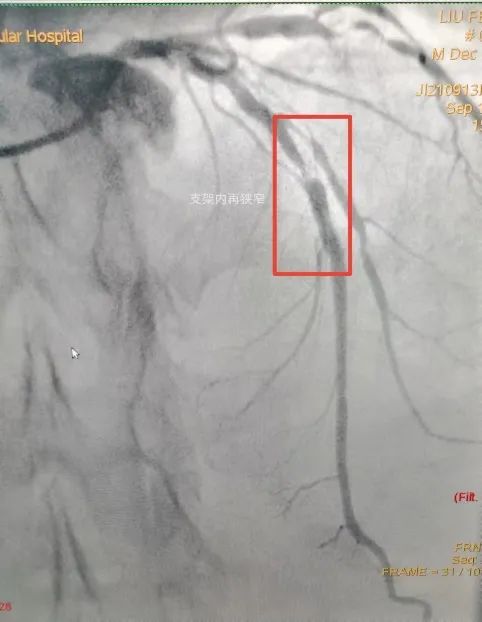

1.支架内再狭窄首选药物球囊

支架内再狭窄是指植入的冠脉支架内或支架两端5毫米节段内,由于血管内皮损伤、内皮功能失调以及新生内膜增殖等原因,导致血管管腔狭窄程度再次超过50%的疾病。由于已经放过支架并且发生了再狭窄,再放支架对于病变来讲并不理想,这时就可以选择药物球囊,通过血管内超声(IVUS)我们可以看到支架内发生了再狭窄,管腔面积不足以维持心脏的供血,患者可能会出现胸闷等症状。

这时我们可以先通过切割球囊来预处理,把支架内的斑块切开,在选择适合的药物球囊贴到病变位置,通常药物球囊要贴45秒以上,它可以把狭窄的血管扩张,并且把药物留在血管壁上。术后造影和ivus都可以看到血管管腔明显改善,达到治疗目的。